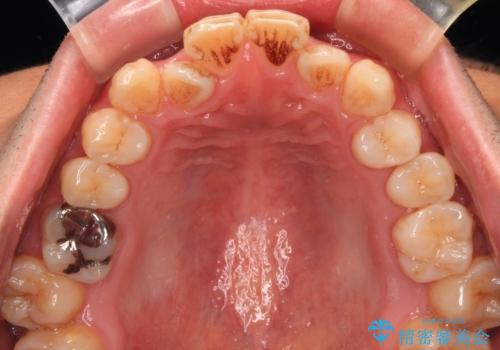

- 口元の突出感が強く、口が閉じにくいことを主訴として来院された患者さんの症例をご紹介します。

前歯部の叢生(デコボコ)も認められ、歯がきれいに並ぶためのスペースが不足している状態でした。

これらの問題を総合的に改善するため、上下左右の第一小臼歯を計4本抜歯し、スペースを確保する治療計画を立てました。

奥歯の噛み合わせがずれている「シザーズバイト」を適正に整えることで、見た目だけでなく機能性も向上し、安定した咬合が獲得できました。

前歯のデコボコが整い、清掃性が向上